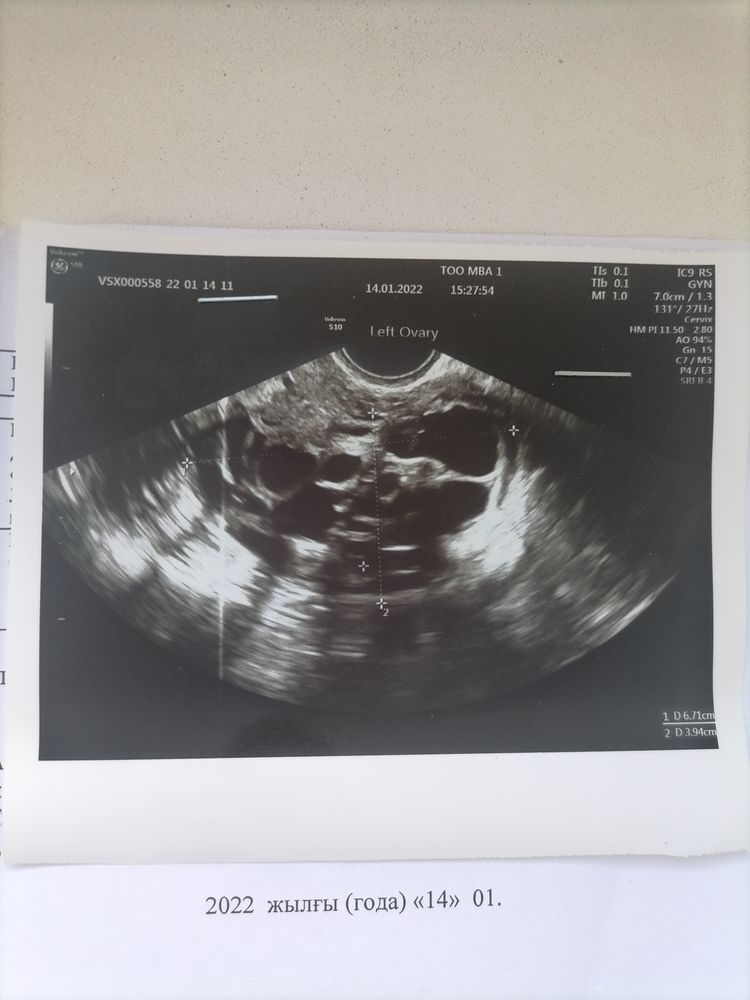

Кто разбирается в узи. Посмотрите пожалуйста. Что скажете???

Юлия Sonnце, написано а второй яичник сам узист не понял что с ним вот и спрашиваю предположение.

Ангелина, сказал на одном 18 фоликул а на втором что то непонятно.... Я так и поняла что зря пришла на это узи....

Таня Таня, ну который 18 - это доминантный,если повезёт то скоро лопнет,пробуйте.они смотрят какие ещё по форме красивые,более круглые.в общем овуляция скоро дня 2-4

Таня Таня, но фолликул же может лопнуть,размер позволяет.

А что сказать. Хорошие яичники, мультифоликулярные

Таня Таня, если добиться овуляции, то не сложно

Это не поликистоз, это МФЯ, а забеременеть сейчас почти с любой проблемой можно....

Таня Таня, вам уже отвечали, что резекцию делали, чтобы рассечь капсулу на яичниках и могла произойти овуляция. Ничего не изменится в плане фолликулярного аппарата.

Нужен укол ХГЧ, Санкт- Петербург Тонкий плохо, толстый тоже 🤯